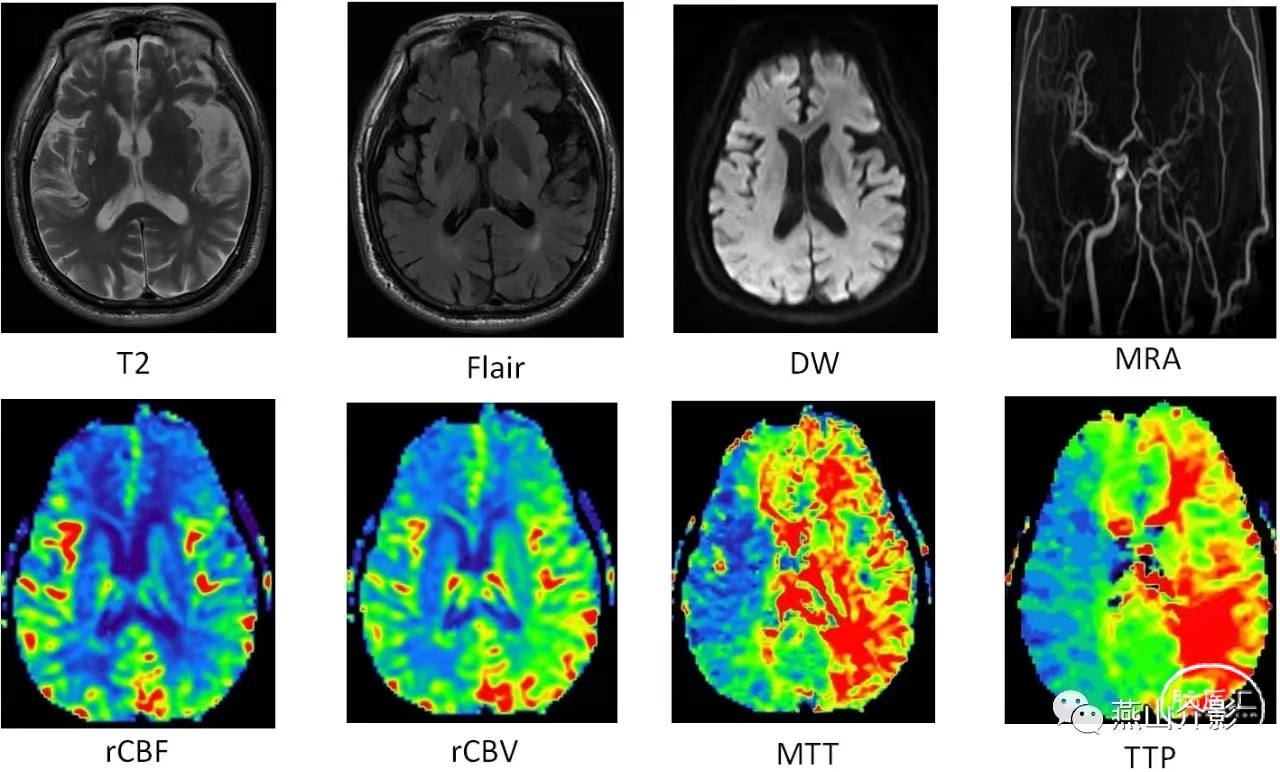

2019-10-17头颅MR双侧基底节腔隙性脑梗死;脑血管CTA左侧颈内动脉纤细;灌注成像提示左侧额顶叶、基底节区rCBV轻度扩张,MTT、TTP显著延长。

2019-10-31复查头颅核磁左侧额叶皮层下点状DW高信号,提示在球囊扩张过程中有小斑块脱落引起颅内栓塞,患者术后未出现症状,未无症状性脑梗死;术后灌注MR左侧额顶叶、基底节区rCBV轻度扩张,MTT、TTP延长较前好转。

2019-11-07复查头颅核磁左侧额叶皮层下点状DW高信号,病灶范围较前缩小;术后灌注MR左侧额顶叶、基底节区rCBV、rCBF较对侧基本一致,MTT、TTP未见明显延长。